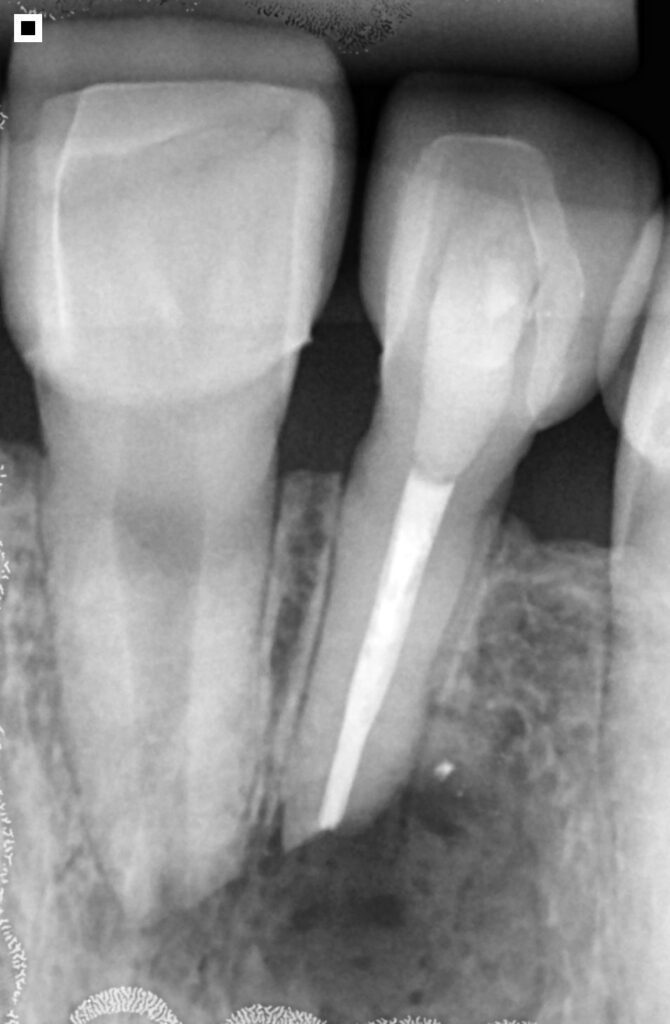

O diagnóstico da necessidade de uma apicectomia se baseia na avaliação clínica e nos exames de imagem. A radiografia e a tomografia computadorizada visualizam com precisão a extensão da lesão.

No caso citado, os exames mostraram claramente a presença de uma lesão no ápice do dente, tanto na região lateral quanto central da raiz, confirmando a necessidade de intervenção cirúrgica.

Apesar de ser um procedimento rápido, a apicectomia é realizada em ambiente cirúrgico, sob anestesia local, com todo o cuidado para garantir conforto e segurança ao paciente. O passo a passo do procedimento inclui:

Uma incisão na gengiva com bisturi, permitindo acesso à região óssea. A exposição da área infectada muitas vezes já revela a gravidade da lesão, seguida da drenagem do conteúdo infeccioso, quando presente.